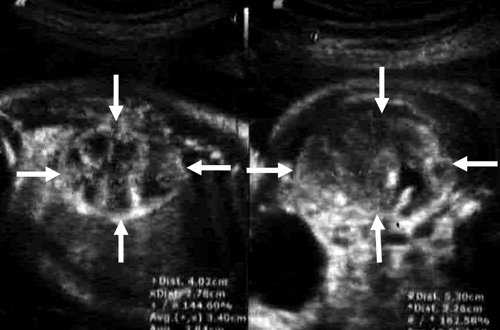

Эхография и РКТ позволяет значительно точнее определить анатомо-топографические и, в какой-то степени, морфологические характеристики нефробластомы (Рис. 1, 2). У всех наших пациентов опухоль была представлена объёмным образованием в виде солитарных масс преимущественно неправильной формы (95,2%). В области опухолевого узла контур почки был выпуклым (14,3%). В 50% обнаруживалась экзофитная зона с фрагментарно выраженной капсулой (71,4%). Эхографическая картина и изображение поражённой почки на РКТ были весьма схожи. Опухоль выглядела как негомогенная структура с преобладанием гиподенситивных очагов (90,5%). Эхографически кальцинаты при нефробластоме выглядят как редкие небольшие высокоинтенсивные сигналы и обнаруживались редко.

Рис. 1. Рентгеновская компьютерная томограмма опухоли почки. Чётко видно, как часть почки замещена опухолевой массой.

Рис. 2. Ультразвуковое сканирование опухоли почки (нефробластома) с очагами распада.